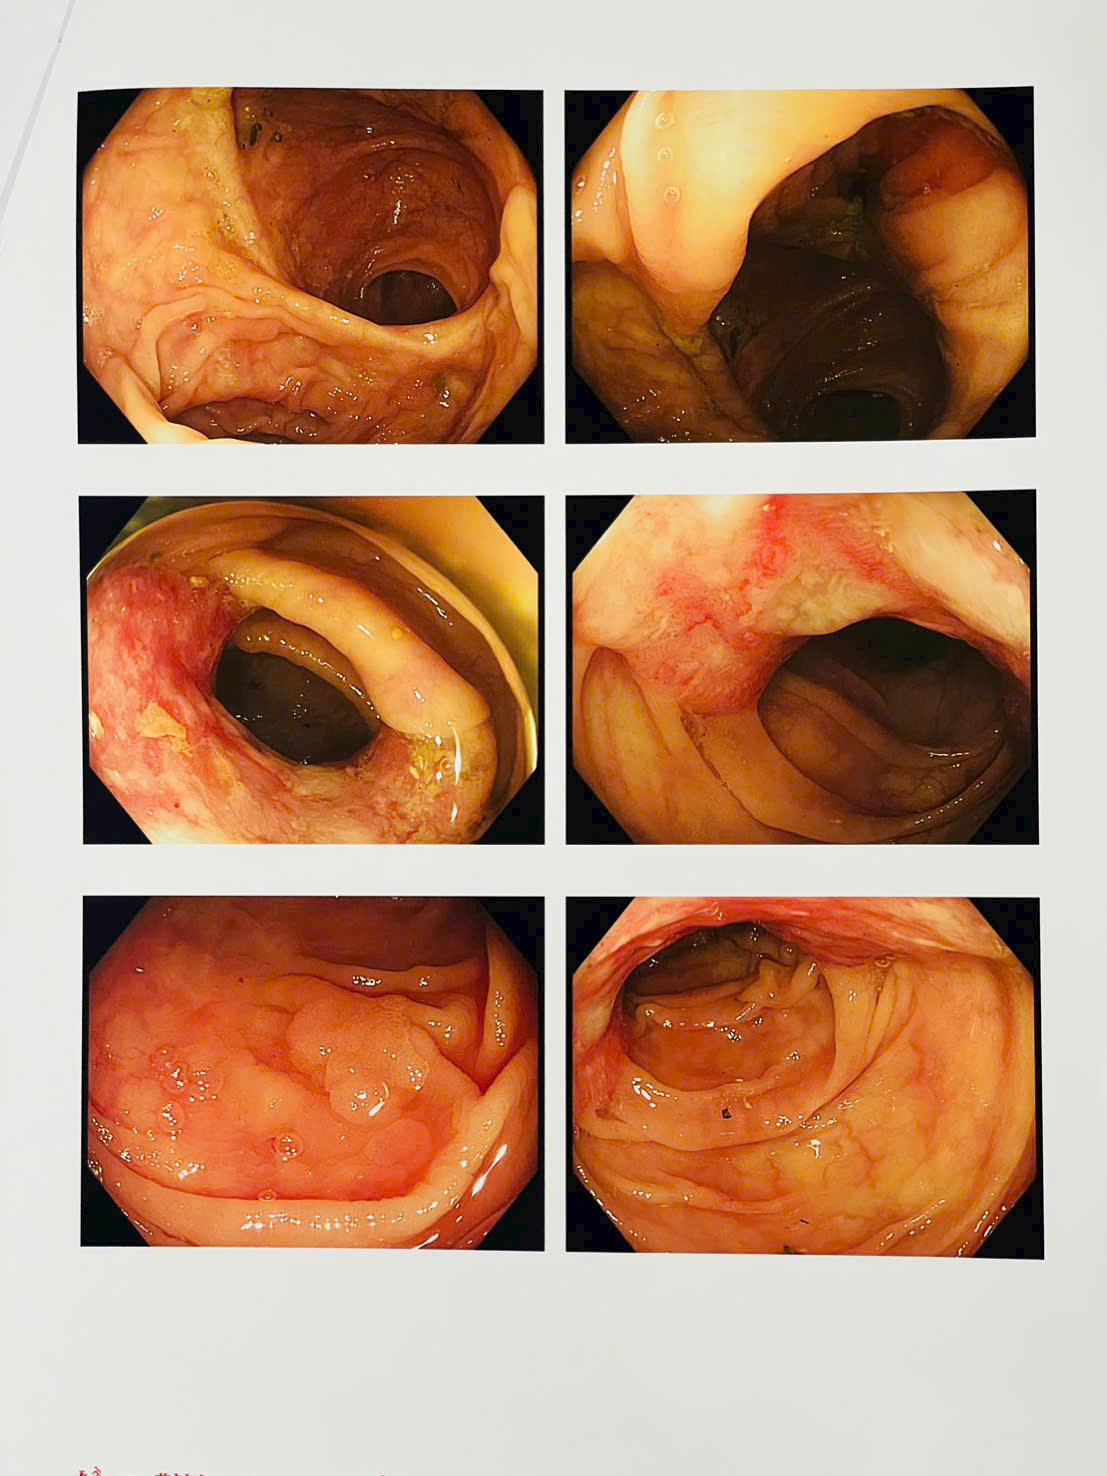

Kết quả xét nghiệm cho thấy bệnh nhân bị thiếu máu nặng, biểu hiện của tình trạng mất máu mạn tính. Trước dấu hiệu bất thường này, các bác sĩ đã chỉ định đánh giá lại toàn diện bằng nội soi dạ dày, nội soi đại tràng, làm các xét nghiệm tổng thể đánh giá nguyên nhân thiếu máu và chụp cắt lớp vi tính (Cắt lớp vi tính 256 dãy) toàn thân. Kết quả phát hiện một khối u sùi mới tại đại tràng, nhiều khả năng là ung thư tái phát (cần kết quả giải phẫu bệnh để chẩn đoán xác định) và rất nhiều polyp đại tràng.

Hình ảnh dày thành đại tràng góc lách nghi u đại tràng trên phim chụp cắt lớp vi tính 256 dãy toàn thân.